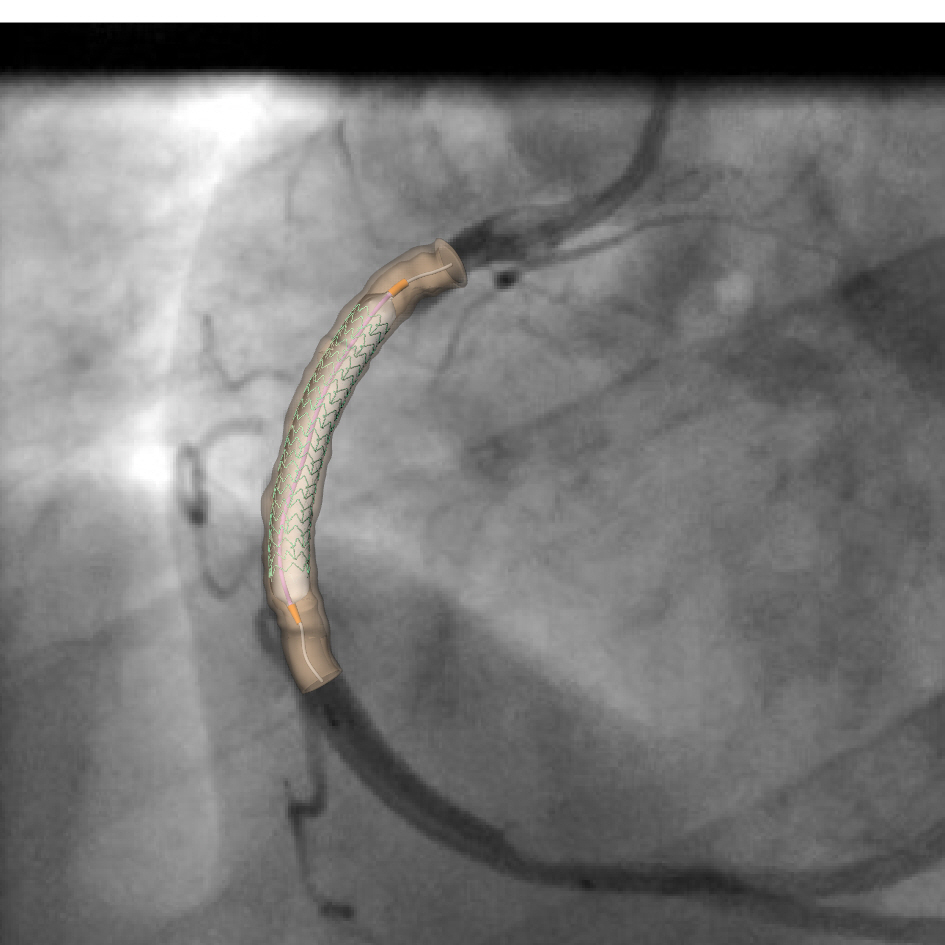

A 28mm stent deployment in a patient specific right coronary artery- The expansion is projected to the angiographic image.

A method has been setup to (i) reconstruct diseased patient specific coronary artery segments; (ii) run many simulations of the deployment of state of the art stents into these segments (the Finite Element Analysis software package Abaqus is used for modelling procedures and demands significant run-times and resources, however, using the 16 core nodes on Iridis, it is possible to perform the simulation of stent deployment through balloon inflation in approximately 60 hours, as opposed to the more than 7 days it would take on a desktop workstation) and (iii) assess the degree of stent malapposition. The aim now is to devise a stent delivery system that can mitigate this problem.